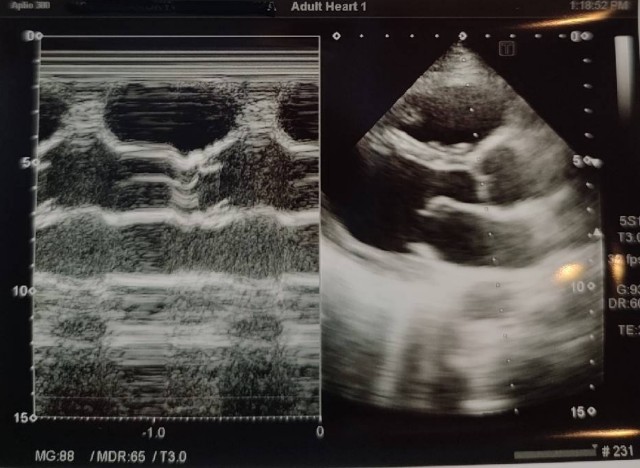

④

大動脈前壁と後壁が平行になっていない。

大動脈と左室に角度があるため、もう一肋間上から描出してみる